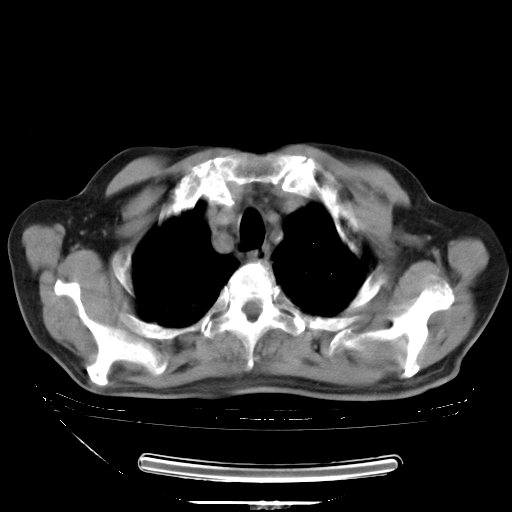

今天复查肺部CT,发现双肺广泛磨玻璃样改变。所以我把3月19日和5月9日相隔50天的肺部CT上传。请大家会诊。

2009年3月19日肺部CT片。

2009年3月19日肺部CT